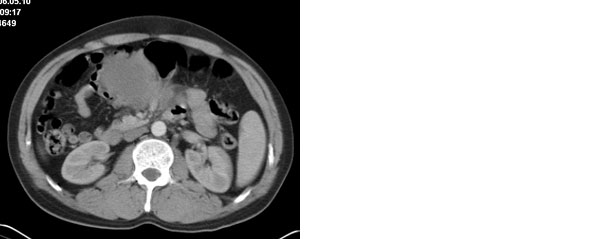

李**,男,46岁,便血1天入院,慢性贫血貌,腹平、软,剑突下压痛,肠鸣音稍活跃,hb大于1g/l,胃镜:慢性浅表性胃炎,b超:1肝内多发性占位 2腹腔内囊性肿块 ,肝内圆形影平扫ct值42.9,动脉期48.6,静脉期58.2,延迟期62.2

影像学表现:1 腹腔前中部、胰腺前方囊实性病灶(个人认为确定有否实性成分存在这是关键,涉及到鉴别诊断,如果是口服阳性造影剂则可明确左侧是不是小肠了),囊性部分囊壁不均,实性部分有强化,与小肠关系较密切,局部小肠受推移;与胰头、胃后壁均有脂肪间隙存在;2 胰腺无异常改变,胰周无渗出;3肝后段包膜下2个小圆形低密度灶,从图像和楼主提供的ct值来看有轻度强化,灶周无片状强化,不似单纯囊肿及肝癌、炎性病变表现;4 腹膜后及腹腔内无淋巴结肿大。

胰腺边界清晰,胰周筋膜不厚,胰周脂肪密度无明显增高;其前方囊实性病灶,边界清晰,增强后实性部分轻度强化;肝内多发边界清晰低密度影,增强后无明显强化(平扫ct值42.9,动脉期48.6,静脉期58.2,延迟期62.2)。

原因:胰头前方,前上腹部巨大囊实性肿物,与小肠关系密切,与胰头及胃壁之间脂肪间隙存在,囊壁不均匀,部分强化,占位效应明显,小肠上段扩张,十二指肠及胃腔内大量食物存留,说明上消化道有部分梗阻。因此,考虑来源于肠道的肿瘤。再结合其病史及肝内改变,这样考虑更有道理。